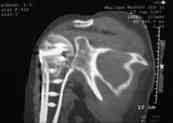

В момент осмотра: нормостеническая конституция, по передней поверхности плечевого сустава – рубец. Рука в положении приведения. Отведение не более 10 град, дальнейшие движения с лопаткой до 20-25 град. Амплитуда сгибания-разгибания 10-15 град. Ротация отсутствует. Пальпаторно - выраженная болезненность над суставом, особенно в проекции клювовидного отростка. При попытках пассивных движений – боль. Рентгенограммы и результаты КТ приложены(b2(3)_xr.jpg, b1(6)_ct.jpg).

Диагноз: неправильно сросшийся в условиях накостного остеосинтеза оскольчатый перелом головки левой плечевой кости (11-С3.2), асептический некроз головки плечевой кости, смешанная артро-миогенная контрактура левого плечевого сустава; демиелинизирующая нейропатия левого локтевого нерва.

Анализ ситуации позволяет считать, что основными причинами контрактуры являются неправильная репозиция фрагментов головки (разворот кверху и кзади), асептический некроз головки плечевой кости (отчетливое склерозирование на СТ).